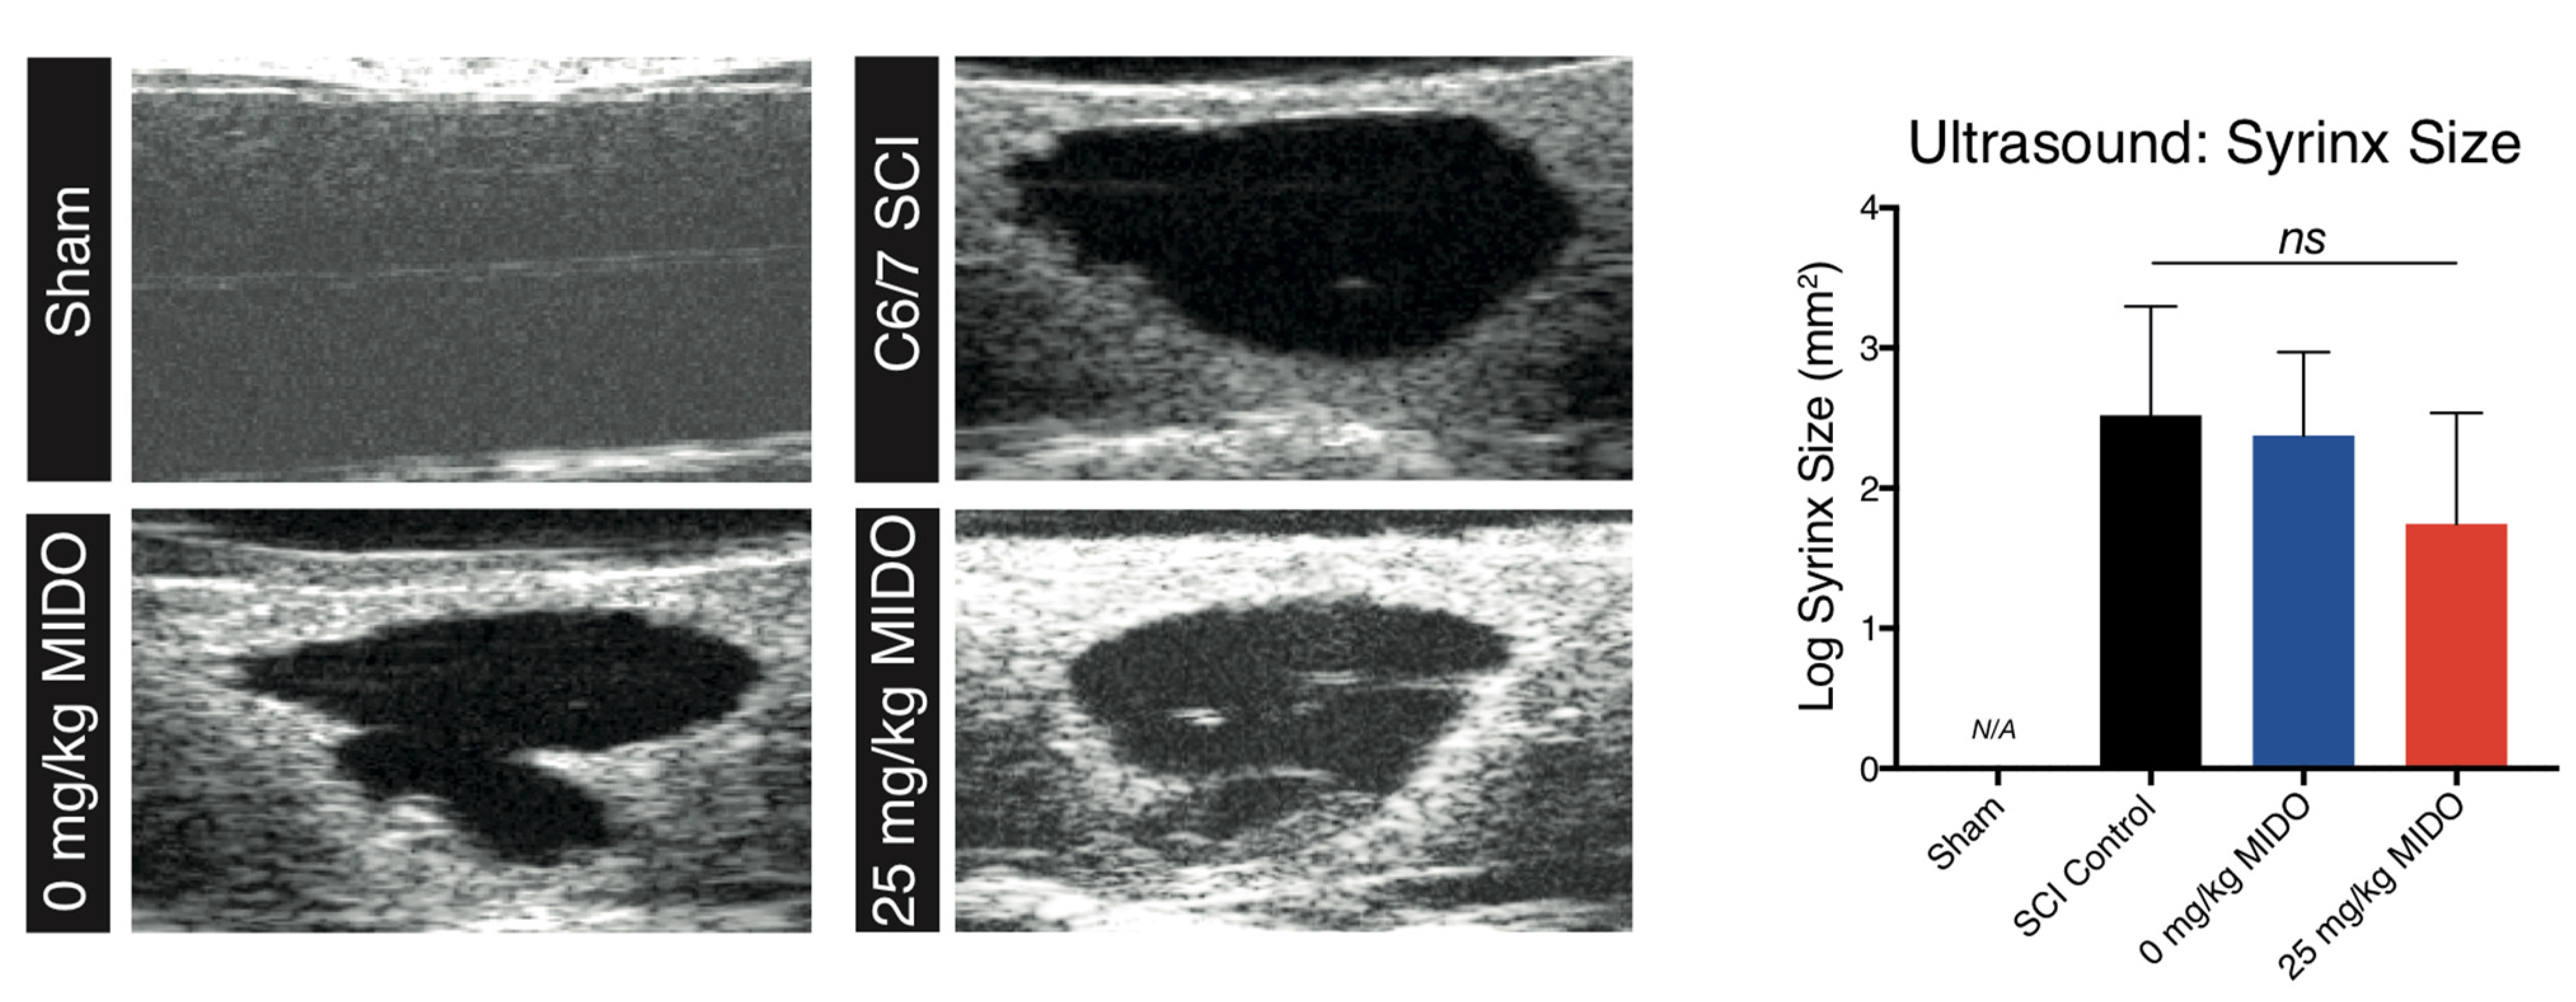

2.8. Ultrasonography

3.4. Histomorphometric Analysis Reveals Improved Tissue Preservation